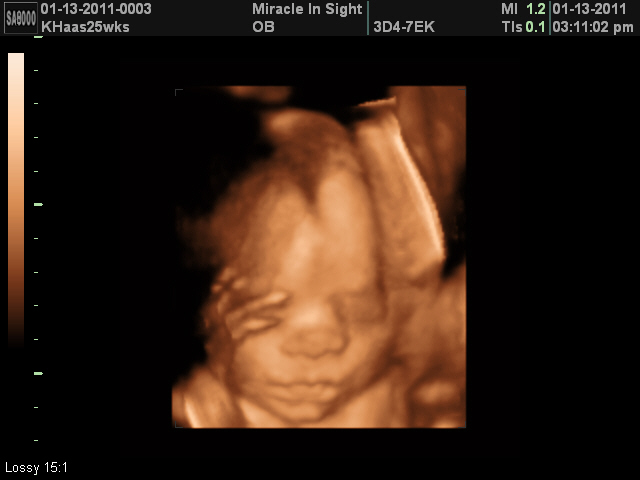

Baby Trying To Chew On Umbilical Cord 3d 4d Ultrasound Youtube